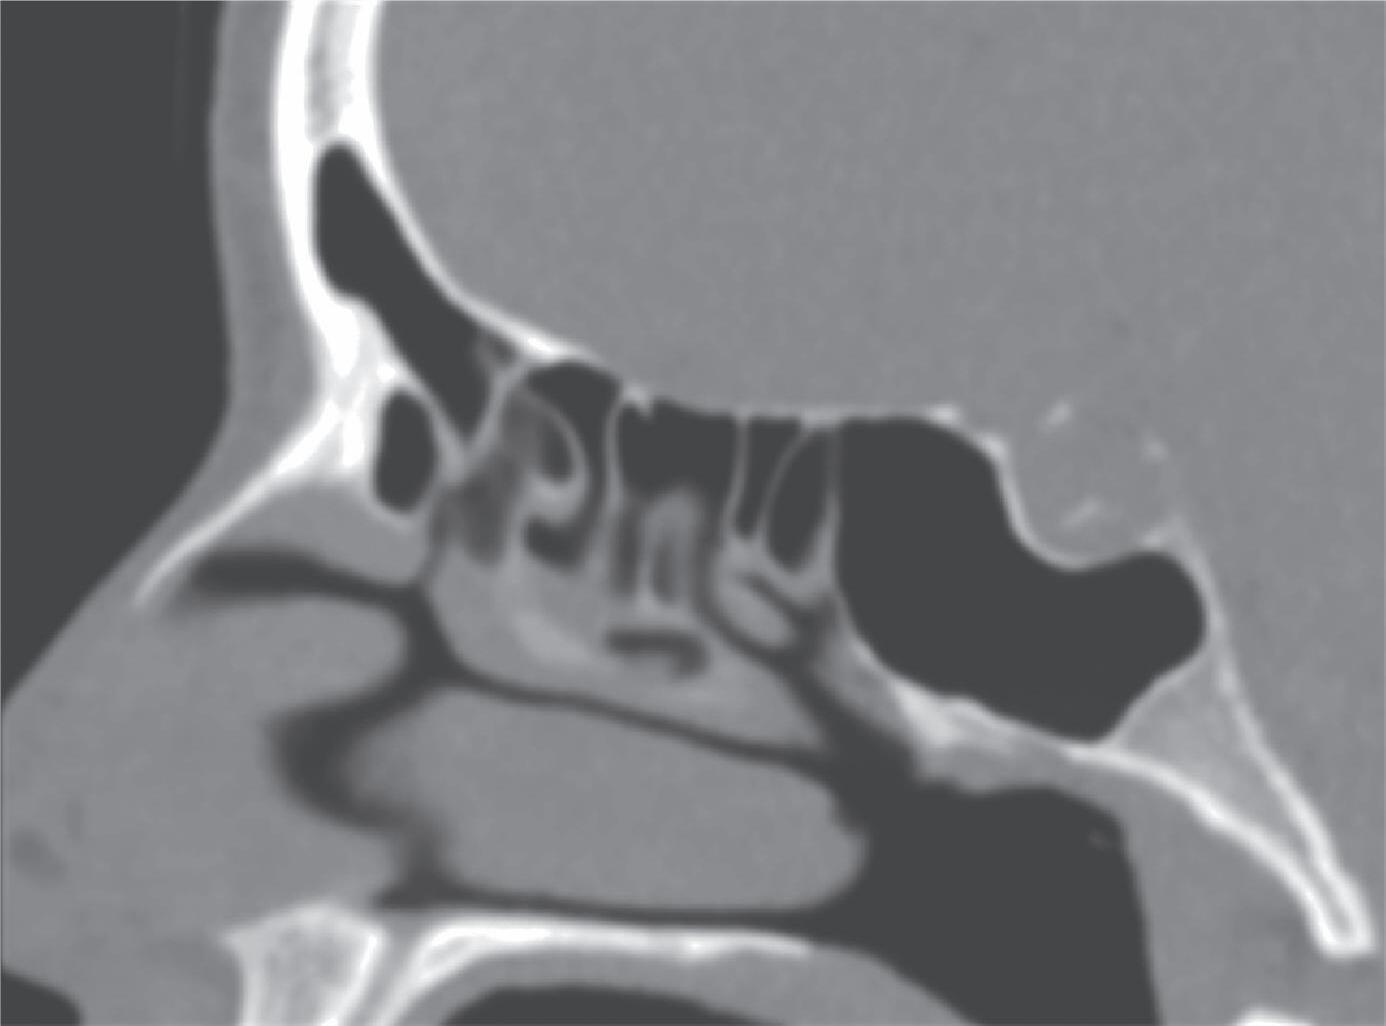

Fig. 1-45. Limites do seio etmoidal: (1) Limite anterior: junção da placa do agger nasi com o processo frontal do maxilar; (2) limite posterior: parede anterior do seio esfenoidal; (3) limite lateral: processo frontal do maxilar mais anteriormente, osso lacrimal (unguis) e a parede medial da orbita (lâmina papirácea) posteriormente; (4) limite superior: piso da fossa anterior, composto anteriormente pela parte medial do processo orbital do osso frontal e posteriormente pelo plano esfenoidal; (5) limite medial: estrutura vertical da concha média; (6) limite inferior: o seio etmoidal comunica-se livremente com a fossa nasal.

Com pouco parênquima funcional, a concha média é o limite medial do seio etmoidal. Atua aerodinamicamente para impedir que o fluxo inspiratório (rápido, frio e seco) penetre nas câmaras de baixa pressão, além de fechar medialmente estes espaços para que o fluxo expiratório possa ser retido tempo suficiente e permitir ação funcional adequada para os seios frontal, maxilar e esfenoidal. Sendo assim, o seio etmoidal apresenta limites bem estabelecidos: